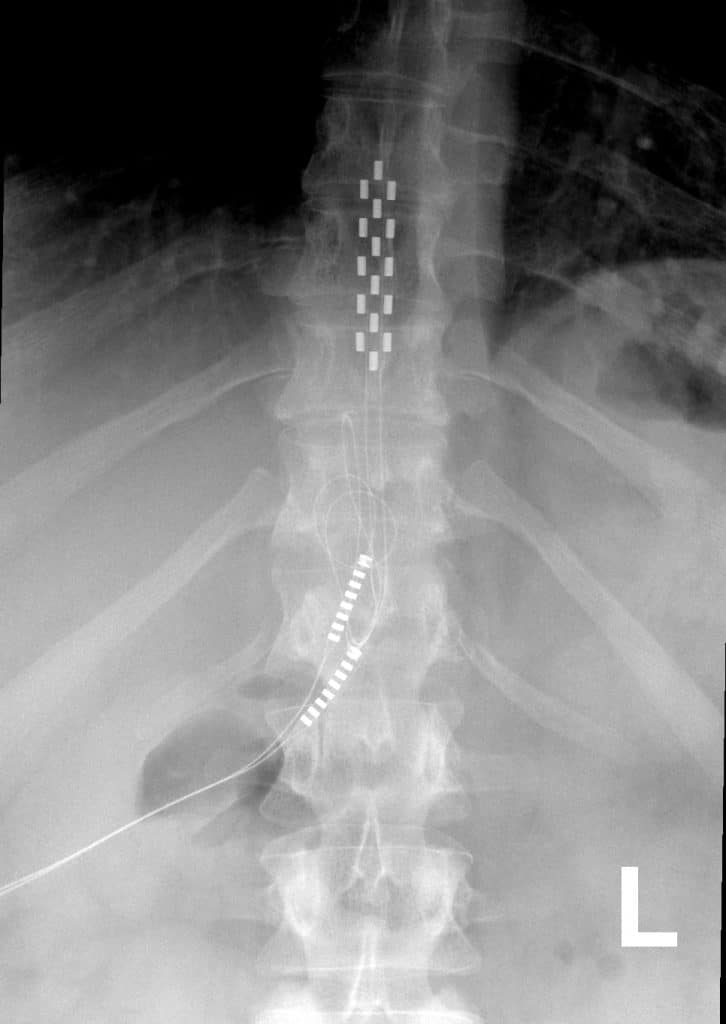

Anterior view X-ray of a Medtronic Spinal Cord Stimulator (SCS) with 5-6-5 paddle lead implanted in the posterior epidural space of the thoracic spine. Image used in compliance with Wikimedia Commons attribution: Mconnell, CC BY 3.0, via Wikimedia Commons